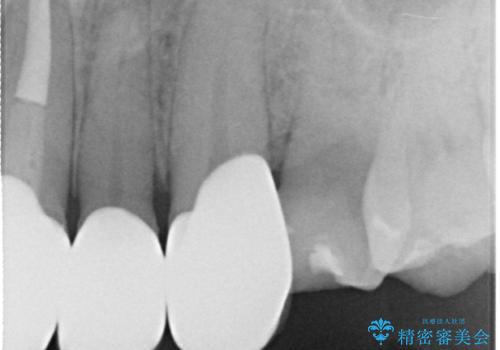

- 昔装着した前歯のかぶせ物を新しくしたいとのことで来院されました。

ご自身の歯とかぶせ物の境目が露出しておりました。

また犬歯の形も気になるとのことでした。

前歯の合計6本をオールセラミッククラウンにする計画としました。

以前に装着されていたものは全て連結されており、清掃性があまり良くありませんでした。

一つ一つを独立したかぶせ物を装着することで、フロスも可能になり、清掃性が向上しました。